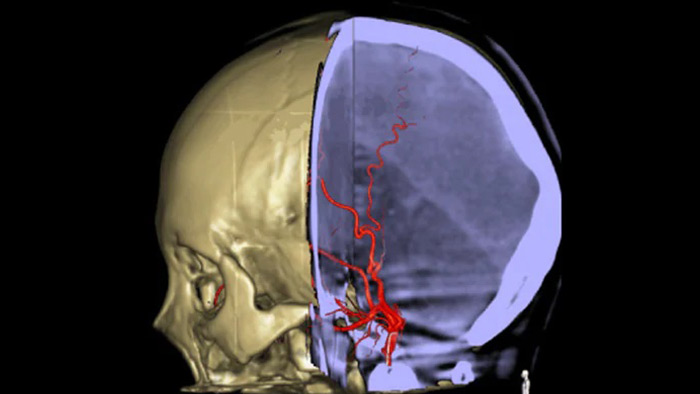

SmartCT Vaso permite la visualización más allá del coágulo con la adquisición de imágenes periprocedimiento de los aspectos del vaso distal en el accidente cerebrovascular isquémico. SmartCT Vaso es una técnica de adquisición basada en una exploración por TAC de haz cónico y una inyección de contraste intraarterial. Mediante la repleción retrógrada, las estructuras de los vasos antes y después del coágulo se vuelven visibles. Además, SmartCT Vaso 3D Roadmap puede utilizarse para visualizar dispositivos de recuperación de coágulos.

Navegación 3D precisa con SmartCT Roadmap

SmartCT Roadmap proporciona referencias anatómicas para permitir la navegación precisa de la guía, el catéter y el dispositivo al coágulo.